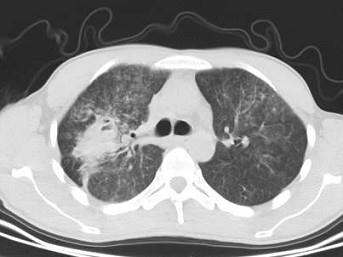

问题 男,32岁,咯血,咳痰一周,胸部CT如图,最可能的诊断为 ( )

选项 A、右上肺结核性空洞并霉菌感染 B、组织胞浆菌病 C、周围型肺癌 D、右上肺感染 E、肺结核

答案 A